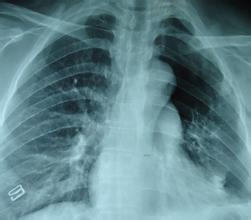

气胸

( pneumothorax )